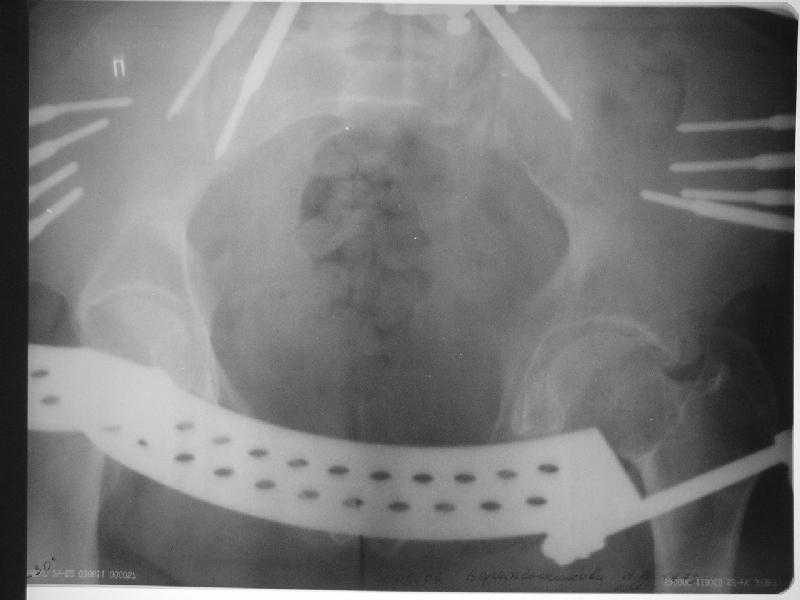

Прооперировали молодую девушку 32 лет спустя 9 мес после травмы. Имелся стойкий болевой синдром, неопороспособность левой н/конечности, моторные и сенсорные нарушения в левой голени и стопе, патологическая подвижность левой половины таза. Первым этапом закрыто в аппарате исправили деформацию ( в течении 2,5 нед). Вторым закрытое введение илиосакральных винтов в крестец (канюллированные 7,2 мм Chm) + туннелизация зоны псевдоартроза спицама Киршнера, реконструкция передних отделов таза, накостный остеосинтез . Аппарат частично демонтирпован, оставлена "передняя рама" После устранения деформации отмечен регресс неврологической симптоматики, уменьшение болевого синдрома. Интересующие вопросы: 1. Прогноз для сращения псевдоартроза крестца. 2. сроки нагрузки весом левой половины таза. Буду очень признателен за ваши мнения по этому поводу.A female 32 y.o. admitted to our unit 9 months after initial injury with pain, inability to bear weight at the left lower limb, sensor and motor disturbances in the left foot and tibia, with mobility of the left hemipelvis.At first closed reduction was performed by an external fixator within 2,5 weeks. After correction her pain decreased and some neurological progress was achieved. Now two iliosacral screws 7,2 mm were inserted, and anterior lesion was fixed by a plate. External fixator was partially unmounted, only anterior frame left in place.Images attached.How would you evaluate chances of healing of the sacrum with the current position?When would you allow weight-bearing of the left leg?THX in advance.

Мне нравится ваша закрытая репозиция девятимесячного ложного сустава, не знаю насчет туннелизации, но шурупы в 7.2 это серёзная конструкция. При стабильной фиксации крестец должен срастись, только я бы держал передний фиксатор до шести недель, костыли, а полную нагрузку разрешить через 12 недель.